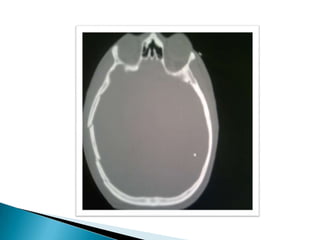

   TC cerebro: Presencia de trazo fracturario a

nivel occipital, temporo-parietal izquierda y

hundimiento de región derecha.

   Cefalohematoma que recorre toda la zona

occipital y temporal

TC cerebro: Presencia de trazo fracturario a nivel occipital, temporo-parietal izquierda y hundimiento de región derecha.  Imagen hiperdensa en región fronto- temporo-parietal izquierda, con desplazamiento de la línea media y borramiento de ventrículos laterales compatible con hemorragia subdural.  Hiperdensidad compatible con hemorragia subaracnoidea.  Cefalohematoma que recorre toda la zona occipital y temporal